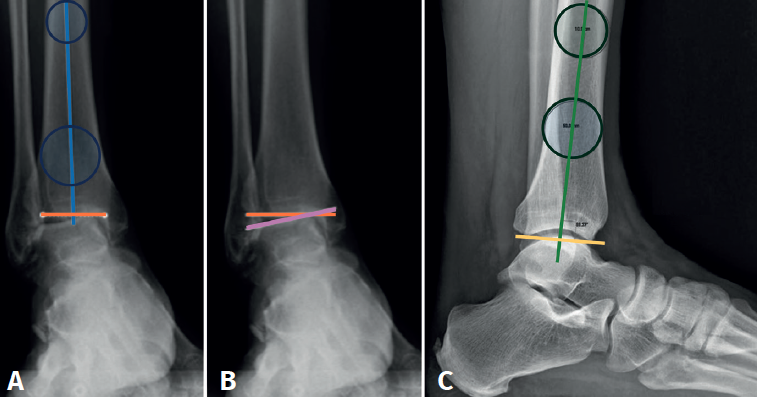

In the anterior ankle projection we evaluate the talar tilt or angle of inclination of the talus, which is increased in incongruent intra-articular injuries (Figure 1).

Figure 1. A: anterior distal tibial angle, between the anatomical axis of the tibia in the posteroanterior plane and the line of the distal joint surface of the tibia; B: talar tilt angle, formed between the line of the tibial joint surface and the line of the talar joint surface. Assesses joint congruency; C: lateral distal tibial angle, between the lateral anatomical axis of the tibia and the line of the lateral distal joint surface of the tibia.